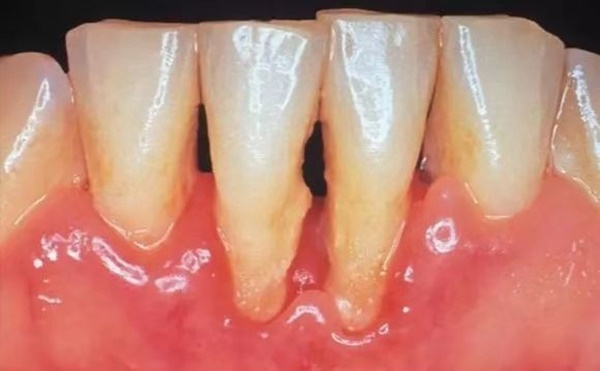

Bệnh viêm nha chu (Periodontitis) là một bệnh nhiễm trùng nướu nghiêm trọng làm tổn thương mô mềm và phá hủy xương xung quanh răng. Viêm nha chu có thể khiến răng bị lỏng hoặc dẫn đến mất răng. Phụ nữ mang thai nếu mắc bệnh tiểu đường thì càng dễ mắc bệnh nha chu hơn.

Biến chứng của bệnh viêm nha chu nguy hiểm hơn nhiều người nghĩ. Theo nghiên cứu, trường hợp bị bệnh nha chu, nếu nhẹ sẽ gây phản ứng co bóp tử cung, nặng có thể dẫn đến sảy thai, sinh non, nhiễm trùng tử cung, hoặc đứa trẻ sinh ra trọng lượng quá nhẹ.